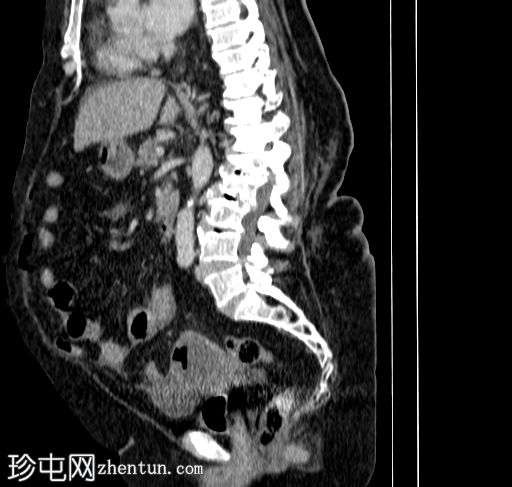

矢状位增强扫描(门静脉期)

宫腔内可见气液平面,符合子宫蓄脓(宫腔内有脓液)。子宫前壁裂开,多个宫外气体灶延伸至腹膜外和腹膜内间隙,提示子宫穿孔。同时可见少量盆腔腹水和少量盆腔脂肪条索状改变。

其他发现:左侧附件囊肿、胆结石、双侧少量胸腔积液。